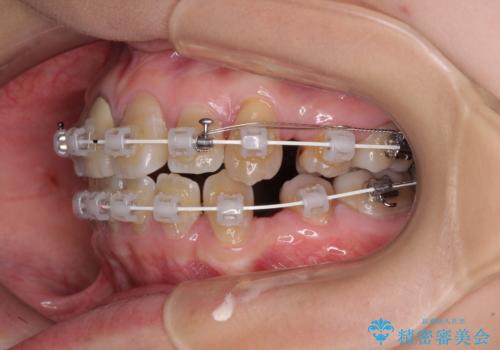

- 審美装置

- 2年5ヶ月

- 10-30回

上下の正中がずれていましたが、抜歯矯正であったので、極力正中位置を合わせるように治療を進めて行きました。

顎間ゴムの使用などにより、正中位置を改善することができました。